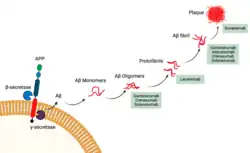

Die Mechanismen der Krankheit sind nicht vollständig verstanden. Der therapeutische Ansatz von Anti-Amyloid-Antikörpern basiert auf der Amyloid-Hypothese: Laut dieser geht die Krankheit von einzelnen Aβ-Proteinen (Aβ-Monomere) aus, welche sich über Zwischenstufen zu Aβ-Plaques zusammenlagern. Dies soll den Anstoß für eine Kette von Veränderungen geben, an deren Ende der Untergang von Nervenzellen steht, wodurch die Symptome verursacht werden. Die Bildung von Plaques erfolgt dabei schrittweise: Aβ-Monomere lagern sich zusammen und bilden Aβ-Oligomere, diese verklumpen über Protofibrillen und Fibrillen letztlich zu Aβ-Plaques.[1] Diese Aggregate lassen sich 10 bis 20 Jahre vor den ersten Symptomen bildgebend darstellen, andere Veränderungen wie die Bildung von neurofibrillären Tangles aus Tau-Proteinen können wenige Jahre vorher nachgewiesen werden.[2] Die Hypothese ist in Details und auch grundsätzlich[3] umstritten.[1]

Anti-Amyloid-Antikörper binden an bestimmte Stellen (Epitope) der Aβ-Spezies, um diese für Mikroglia erkennbar zu machen. Diese Immunzellen können die markierten Ziele anschließend abbauen (Phagozytose). Die Affinität zu den verschiedenen Aβ-Spezies unterscheidet sich dabei zwischen Wirkstoffen, möglicherweise wird zudem die Phagozytose von nichtmarkierten Aβ- und/oder Tau-Spezies eingeleitet.[4] Alle bis einschließlich 2024 zugelassenen Wirkstoffe (Aducanumab, Lecanemab, Donanemab) zielen auf Protofibrillen und größere Aβ-Spezies und reduzieren Plaques deutlich, teils unter die Nachweisgrenze.[5]